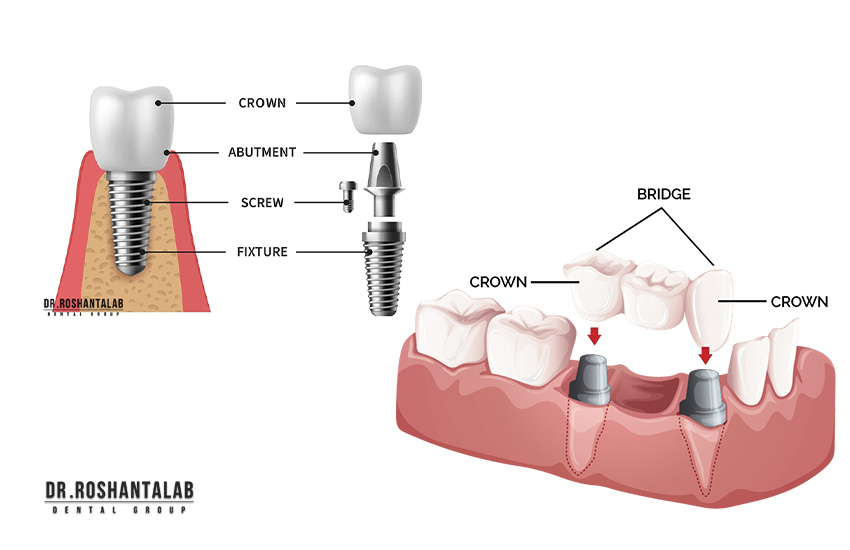

![لمینت دندان [انواع، مراحل، مزایا، هزینه] + مشاوره تخصصی](/storage/posts/covers/2026/01/06/ca650cdb72bf540229b3e1ecdae26e85bfdae68c1df07ce39c12705bfcfb0c44.webp)